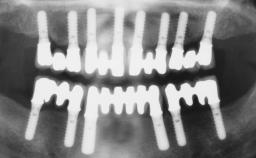

| Case Type | Single-Tooth Space |

| Jaw | Maxilla |

| Area | Anterior |

| # of Teeth | 1 |

Surgical SAC classification

| SAC Level | - |

|---|---|

| Defining Characteristics | - |

| Modality | - |

| Placement Protocol | - |

| Tooth Site | - |

| Socket Morphology | - |

| Socket Integrity | - |

| Bone Volume | - |

| Anatomic Risk | - |

| Esthetic Risk | - |

| Complexity | |

| Risk of Complications | - |